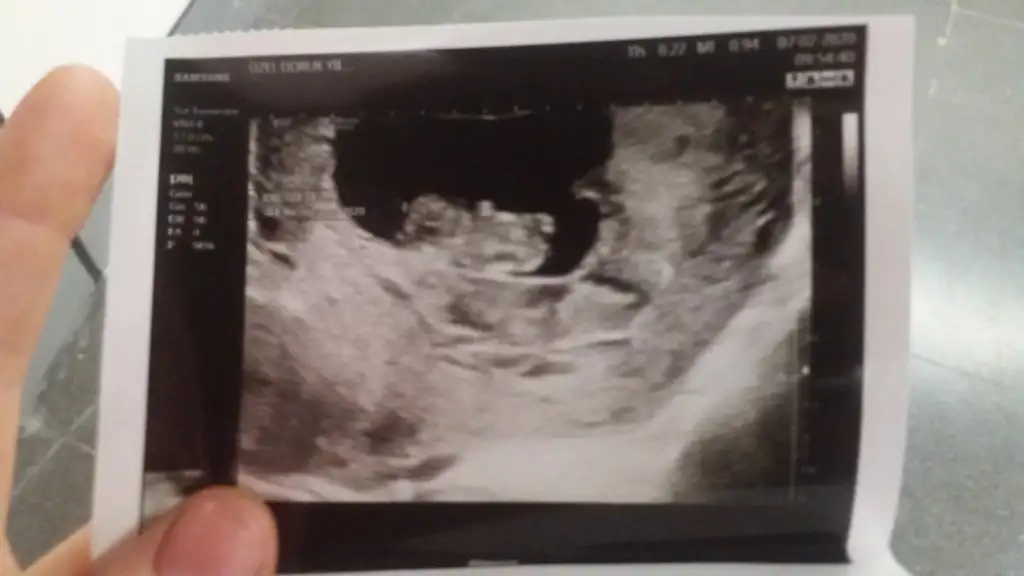

Bugün doktora gittik ama yüzüstü yatıyordu bir şey göremedik :))) siz keseye bakıp erkek, 12. Haftaya bakarak kız demiştiniz. Şimdi 17. Haftadayız:) ben erkek hissediyorum dedim doktor bence tam tersi sanki dedi 😁 sizce ne olabilir Ikra meyra Ikra meyra

12 de Kız tahmin etmiştim hale kız diyorum